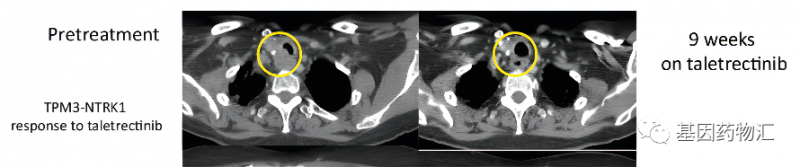

这位TPM3-NTRK1融合突变的转移性甲状腺乳头状癌患者,通过Taletrectinib(AB-106)治疗取得了相当不错的疗效。他用药后的缓解持续时间已经达到了33.4个月,并且至结果发布时,仍在刷新着这个数据,持续保持临床缓解!

他之前已经接受过非常多的治疗,包括甲状腺切除术、放化疗、放射性I-131治疗、索拉非尼治疗,甚至接受过了3个靶向治疗联合或不联合免疫检查点抑制剂的Ⅰ期临床试验。能够继续达到这样长的缓解期,疗效可谓相当出色。